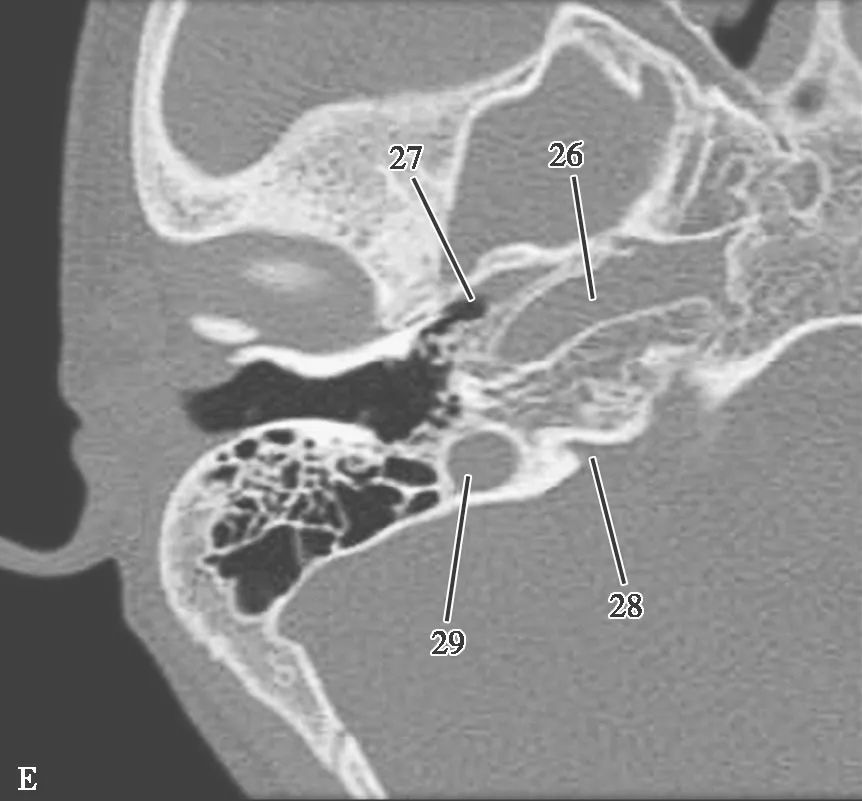

耳部及其周围的重要解剖结构 (CT横断面)

A.上骨半规管层面;B.外骨半规管层面;C.前庭窗层面;D.耳蜗层面;E.颈动脉管层面1.上骨半规管;2.弓形下窝;3.总骨脚;4.后骨半规管;5.外骨半规管;6.内耳道;7.耳蜗;8.面神经管迷路段;9.膝状神经节;10.前庭;11.上鼓室;12.乳突窦入口;13.乳突窦;14.鼓膜张肌;15.锤骨头;16.砧骨体;17.前庭窗;18.前庭导水管;19.圆窗;20.鼓岬;21.锤骨颈;22.砧骨长脚;23.面神经隐窝;24.锥隆起;25.鼓室窦;26.颈动脉管;27.咽鼓管;28.耳蜗导水管;29.颈静脉球